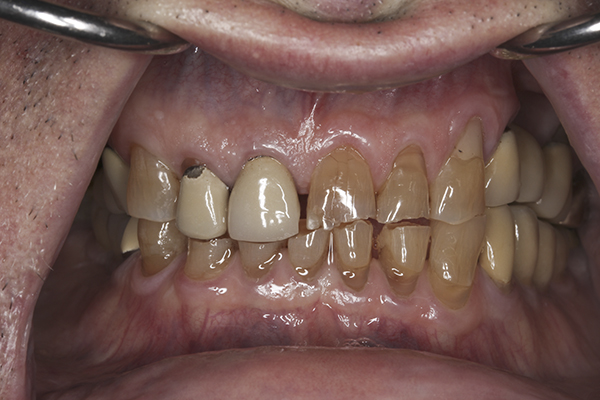

(10.) Preoperative anterior, closed view. Note the end-to-end occlusion of the anterior teeth and the wear on the incisors and centrals resulting in no anterior or canine guidance.

Figure 10

(24.) Provisionals, anterior, closed view.

Figure 24